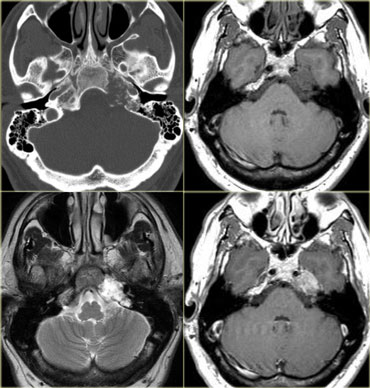

Cerebello-pontine angle

Common CP Angle Tumors are listed in the table on the left.

On the left a 52-year-old male with hearing loss on the right.

The images show an unusual cystic mass with enhancing septations.

There is also some enhancement within the internal acoustic canal.

Based on the images the most likely diagnosis would be a cystic schwannoma, but this happened to be an uncommon, cystic presentation of a meningioma.